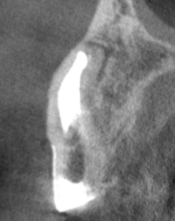

根管長測定

気温や湿度などの環境変化、経年変化によって生じる測定値の誤差を自動で補正し、安定した測定精度を保つオートキャリブレーション機能を搭載。

ドライでもウェットでも根管内の状態に影響されない高精度な測定で治療をサポートします。

根管長測定機能によって根管内のチップ電極の位置を設定し、フットスイッチを踏むことで1秒間のHFCが行えます。